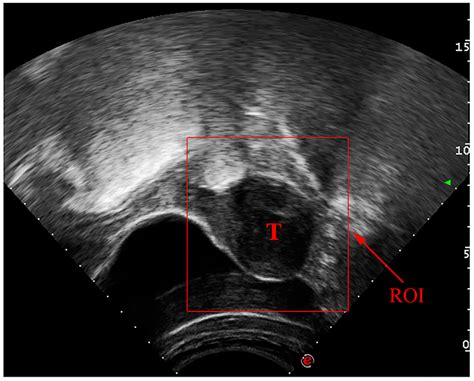

Uterus Test Videos often delve into these conditions, explaining their symptoms, causes, and diagnostic methods. For instance, a video might show how a transvaginal ultrasound is used to detect uterine fibroids or how a biopsy is performed to diagnose uterine cancer.

• Ultrasound: Uses sound waves to create images of the uterus and surrounding structures.